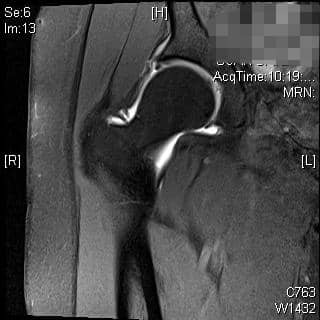

एमआरआई और सीटी का उपयोग एसिटाबुलम और समीपस्थ फीमर के आगे के मूल्यांकन के लिए किया जा सकता है। ये अध्ययन एसिटेबुलर संस्करण और नरम ऊतक के प्रभाव का बेहतर मूल्यांकन प्रदान कर सकते हैं या प्रीऑपरेटिव प्लानिंग में मदद कर सकते हैं। एमआर आर्थ्रोग्राम ऊरु गर्दन के कैम घाव के निदान में भी सहायता कर सकता है, लैब्रम या उपास्थि का आकलन कर सकता है। रेडियल अनुक्रमण सबसे अच्छा है, एक असामान्य लैब्रम कुंद दिखाई देगा या इसके आधार पर बढ़े हुए संकेत के साथ दिखाई देगा। 3, 4 एसिटैबुलर रेट्रोवर्जन के कारण पिंसर का प्रभाव, शुरू में लैब्रल विफलता दिखाएगा, जिसके बाद एक कॉन्ट्राकूप तंत्र के परिणामस्वरूप पोस्टरोहीन एसिटेबुलर कार्टिलेज में छोटे, पतले घाव होंगे। 5 इसे क्रॉस-ओवर संकेत, पीछे की दीवार के संकेत, या रेडियोग्राफ़ पर एक नकारात्मक खट्टा कोण के साथ पुन: प्रदर्शित किया जा सकता है। एमआरआई में कुंद लैब्रम, ऊरु गर्दन पर चुंबन घाव, पीछे के एसिटेबुलर कार्टिलेज का घिसना, या एक रेट्रोवर्टेड एसिटाबुलम प्रदर्शित होगा। ऊरु गर्दन के घावों के कारण कैम का प्रभाव, उपास्थि की प्रारंभिक विफलता को दर्शाता है, जिसके बाद लैब्रल फट जाता है। पार्श्व एक्स-रे पर सिर-गर्दन ऑफसेट में कमी, ऊरु गर्दन पर अतिरिक्त हड्डी की आकृति और बढ़े हुए अल्फा-कोण का आकलन निदान में सहायता कर सकता है। एमआरआई पर लैब्रम अपने आधार पर फटने का प्रदर्शन कर सकता है, एक असामान्य ऊरु सिर-गर्दन समोच्च स्पष्ट हो सकता है, या उपास्थि प्रदूषण स्पष्ट हो सकता है। रोगी 80% मामलों में कैम और पिंसर दोनों के साथ पेश होंगे, हालांकि एक रूप आमतौर पर प्रमुख होता है। 2

रोगी एक 39 वर्षीय महिला है जिसमें महत्वपूर्ण दाहिने कूल्हे का दर्द है जो गैर-प्रभाव लोडिंग व्यायाम, गतिविधि संशोधन और स्टेरॉयड इंजेक्शन के साथ रूढ़िवादी उपचार के बावजूद बना रहता है। वह गहरी कुर्सियों से बाहर निकलने और धुरी गतिविधियों से सबसे ज्यादा परेशान है। उनका एमआरआई किया गया था, जिसमें लैब्रल टियर दिख रहा था।